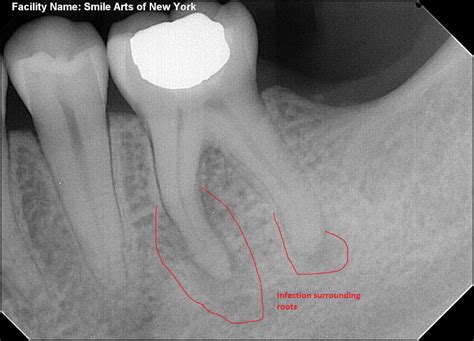

1. Diagnosis and X-rays: The dentist will assess the tooth's condition and determine the extent of the infection.

An emergency root canal becomes necessary when the soft tissue inside your tooth—known as the pulp—becomes severely infected or inflamed. This internal chamber contains nerves, blood vessels, and connective tissues. When bacteria penetrate this area due to deep decay, a crack in the tooth, or trauma, the resulting pressure leads to extreme discomfort.